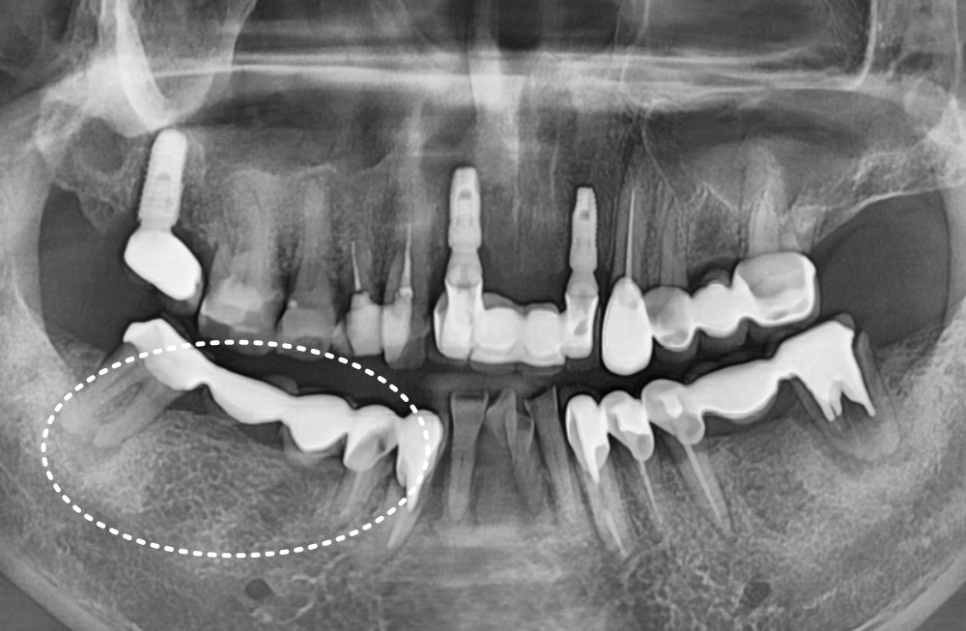

결국, 남아있는 뿌리 3개를 발치하고

튼튼한 임플란트 3개를 식립하는 것으로

치료 방향을 잡았습니다.

250610

설상가상이라 했던가요.

반대편인 왼쪽 어금니 브릿지(#35~37)마저

탈락해버렸어요.

살펴보니 이곳 역시 잇몸 뼈가 녹아내려

치아가 심하게 흔들리고 있었습니다.

왼쪽 역시 살릴 수 없는 치아를 정리하고,

임플란트로 진행했습니다.